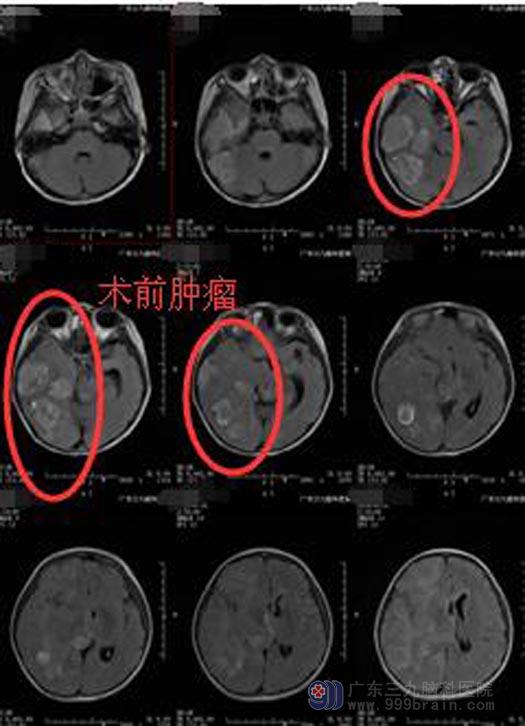

一周前她再次出现之前同样的症状,并且发作频率增多。入住广东三九脑科医院综合神经外科时精神状态较差,嗜睡,间断有呕吐,左侧中枢性面瘫。头颅MR及ASL检查结果:1.右侧颞叶多发占位性病变,并累及右侧基底节区、双侧丘脑及胼胝体膝部偏左侧;结合MRS检查考虑为恶性肿瘤性病变,并脑脊液播散转移,2.右侧大脑镰下疝形成;3.右侧上颌窦及筛窦炎症;4.双侧中耳乳突炎症。考虑恶性肿瘤,体积较大。

小瑜的病情重,年纪小,需尽快手术治疗,她的父母知晓病情后,同意在全麻下行“右侧颞枕岛叶基底节区多发占位病变切除术”。术中见肿瘤组织呈灰褐色,质软,边界不清,血供丰富,显微镜下分块全切肿瘤,手术过程顺利;术后小瑜神志清醒,应答正确,肢体活动正常,未见癫痫发作症状,顺利出院,等待后续的进一步治疗。